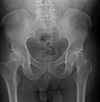

38

What distinctive vertebral body appearance is noted?

H-shaped vertebrae (DDx: Sickle cell anemia, thalassemia)

39

Give 2 differentials in order of likelihood.

1. Sickle cell anemia 2. Thalassemia